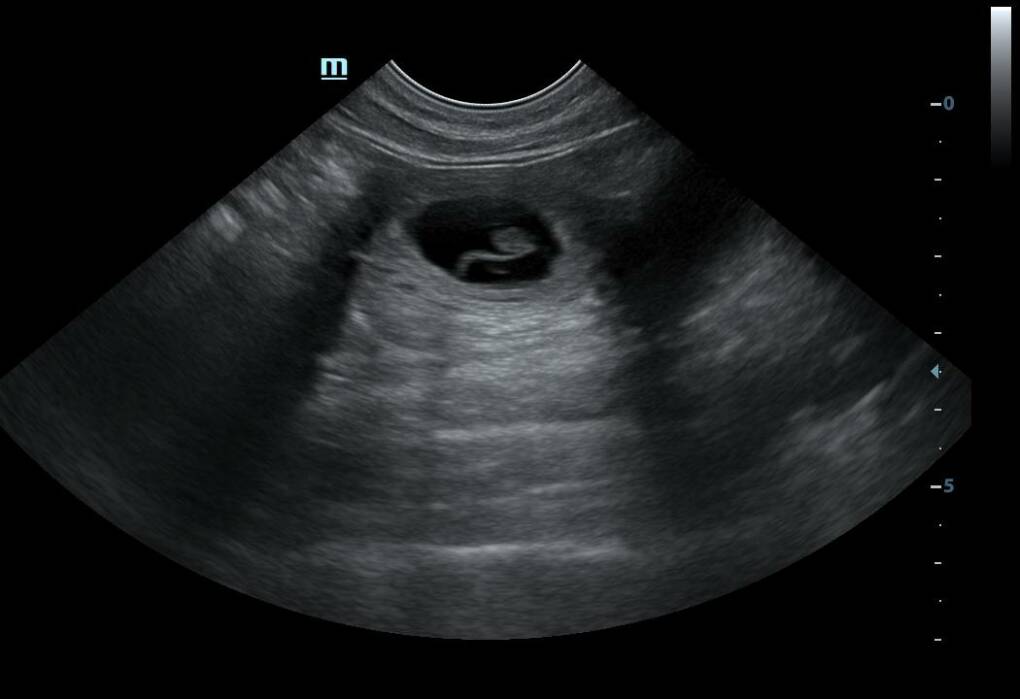

15.03.2024 | Wir freuen uns sehr, Hope ist heute geschallt worden und wir haben ganz viele Kleine Babys sehen können. Nun heißt es warten und hoffen, das wir eine gute Restträchtigkeit haben und eine schöne leichte Geburt mit vielen gesunden süßen kleinen L´s! ![]() |

26.07.2021 | Es ist vollbracht heute hatten wir das erste Utraschall mit unseren Süßen Hope. Zu unserern großen Freude konnten wir dann einige kleine Fruchtblasen erkennen und somit werden wir Anfang September unseren J-Wurf erwarten.